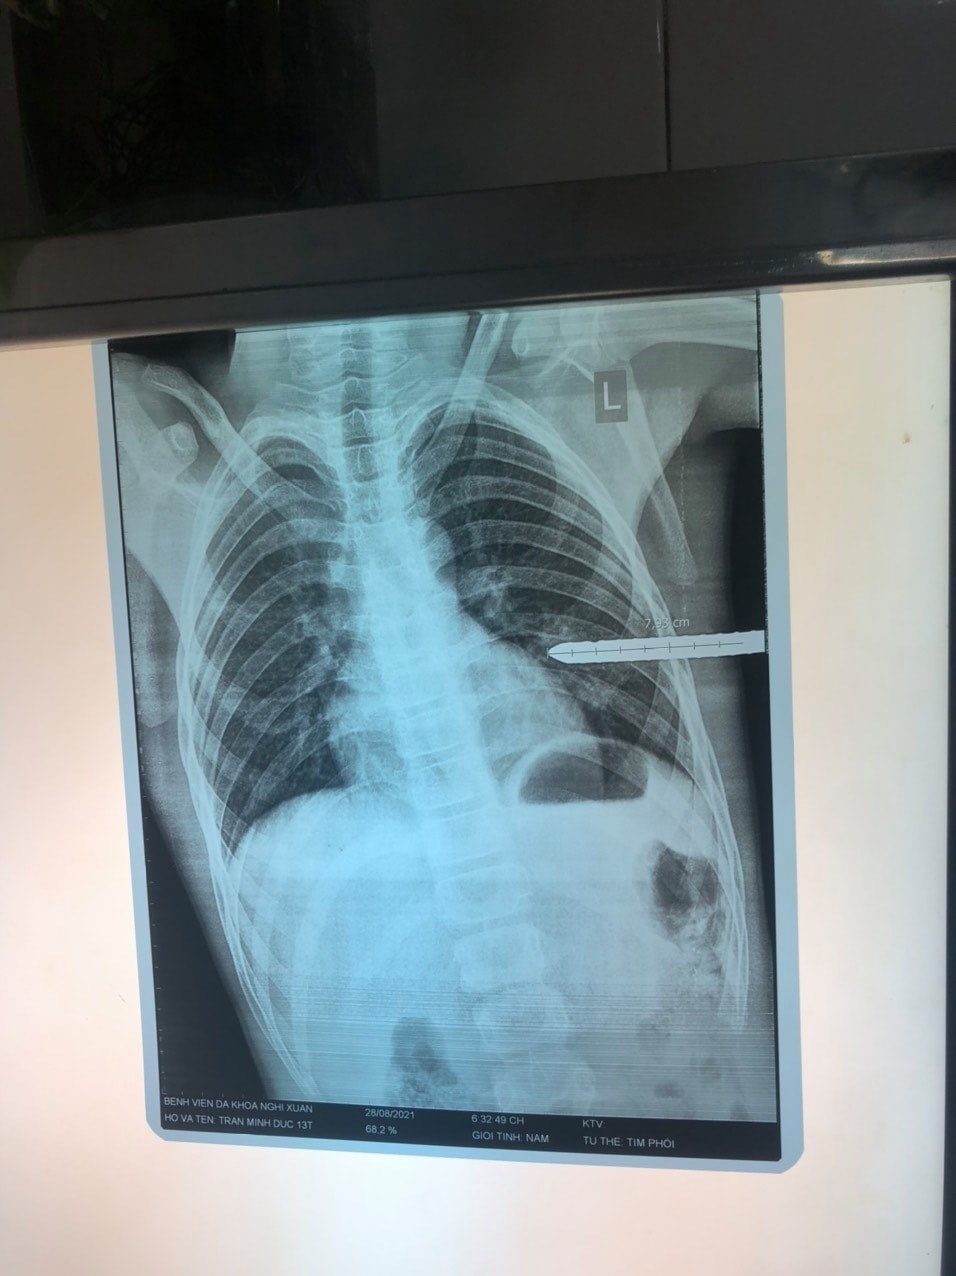

Hình ảnh chụp X-quang cho thấy thanh sắt đâm thấu ngực trái, gây tràn khí phổi. Ảnh: BVCC.

Thanh sắt có kích thước lớn, dài khoảng 1 m xuyên vào ngực trái, ở đường nách giữa, khoang sườn 5-6. Vết thương rỉ máu quanh miệng.